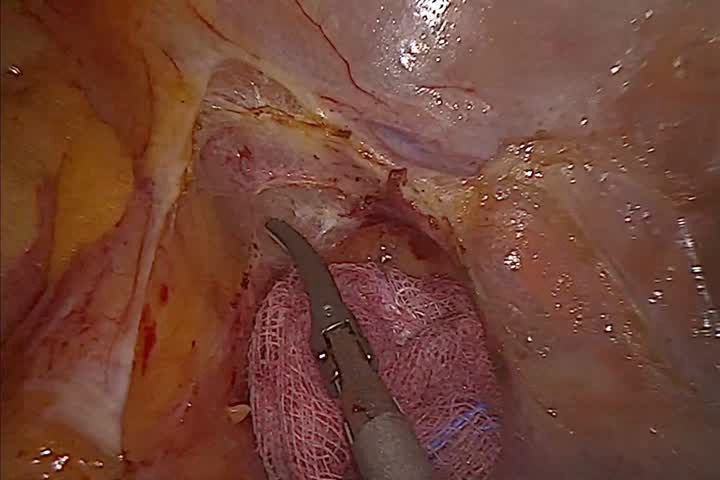

Watch the Full VideoLateral abdominal wall hernias refer to structural weaknesses in the muscles and fascia along the side of the abdomen. These defects are relatively rare and can be challenging to diagnose due to their location and often subtle presentation. Patients may experience localized pain or discomfort. The aim of this presentation is to describe a case of a patient with a lateral Spigelian hernia and to demonstrate a minimally invasive technique for its correction.